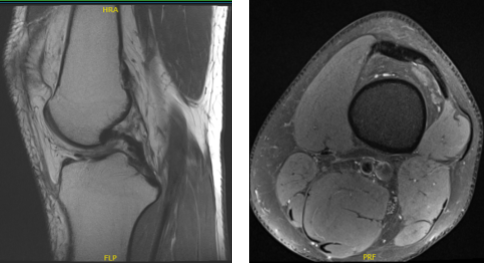

But his knee makes him uncomfortable. MRIs were advised for us to see the correct diagnosis of his condition. For now, I advised patients to take Flexeril and Mobic for pain medication.

MRI Impression as follows: Oblique tear in the posterior horn of the medial meniscus extending to the inferior surface, peripheral third. Edema in the superolateral aspect of Hoffa’s fat pad suggestive of Hoffa’s fat pad impingement and elevated TT TG distance of 16 mm which can be seen in setting of patellofemoral maltracking and small popliteal cyst.